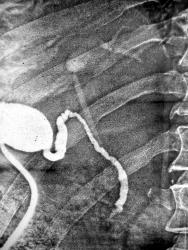

Пожелтел за 2 недели до исследования. Выполнена лапароскопическая холангиография для установления природы мех. желтухи. Ваше мнение?

Имееется:

1.Холецистохолангиография;

2. Контрастирован только пузырь, пузырный проток и холедох;

3. Общий печеночный проток контрастирован слабо;

4. В области бифуркации неясное сужение, ближе к циркулярному;

5.Контрастирован умеренно расширеный левый печеночный проток и его система; правый - не просматривается;

6. Контраст в 12 п кишке не прослеживается.

Вывод: препятствие, вероятнее всего в области бифуркации с переходом на правый печеночный проток; наиболее вероятная причина -опухолевое поражение в указангной зоне.

Примечание: степень контрастирования в\печеночных протоков слабая, вероятность ошибки велика, особенно учитывая наличие только одного снимка.

На операции высокая стриктура обшего печеночного протока, механическая желтуха, природа так и осталась не ясной, хирурги сказали по типу рубцовой перетяжки протяженностью 2-3 мм.